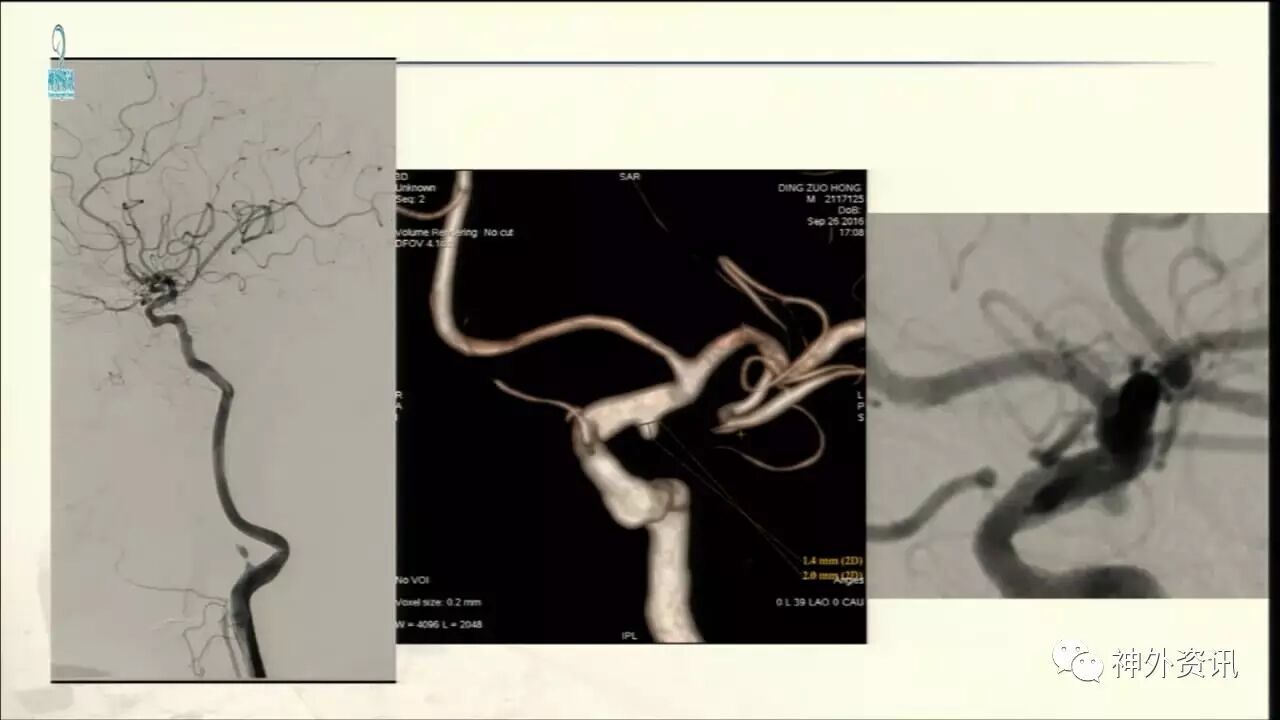

今天“神经介入专栏”为大家分享由上海交通大学医学院附属仁济医院神经外科副主任万杰清教授带来的“颅内小动脉瘤的介入治疗--GALAXY微弹簧圈是一种不错的选择”精彩讲课视频及PPT,欢迎观看、阅读。文章仅代表作者个人观点,如有不同见解,欢迎同道斧正!